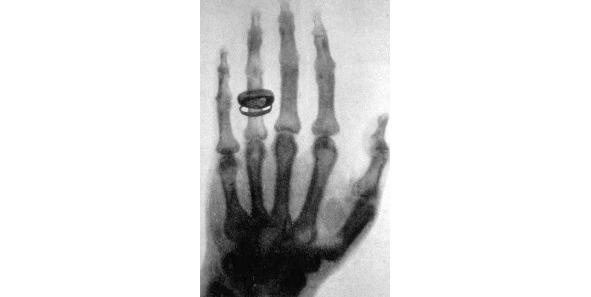

Главное открытие в своей жизни Конрад Рентген сделал 8 ноября 1895 года. Работая в своей лаборатории, он обратил внимание на то, что после включения тока в катодной трубке, почему-то начинает светиться покрытый слоем платиноцианистого бария бумажный экран. Причем происходило это вопреки «здравому смыслу», поскольку трубка была полностью закрыта плотным черным картоном, а значит, свет не мог проходить через него. Он выключил ток  свечение прекратилось, включил  экран снова засветился! И тогда он сделал вывод, что в трубке возникают икс-лучи, которые способны проходить через плотный материал, и заставляют флуоресцировать особые вещества. Причем в зависимости от вида материала и его толщины, преграда пропускала больше или меньше лучей. Как следствие, стало возможным анализировать структуру различных объектов. Установка, разработанная Рентгеном, выполняла совершенно новую функцию  неразрушающий анализ структуры непрозрачного объекта.

Рисунок 2. Первый рентгеновский снимок  рука Альберта фон Кёлликера, 21.01.1896 года